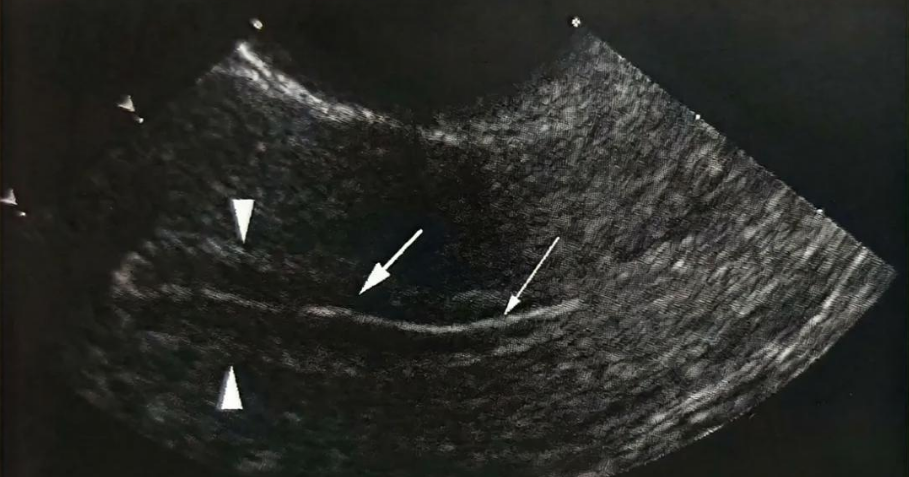

A型内膜常见于增殖晚期。排卵前,雌激素水平增高,功能层内膜增厚,但内膜血管、腺管等结构的数目少、管径细,因此内膜内部的超声反射界面较少、功能层内膜表现为均匀的低回声。低回声的功能层内膜夹在两条高回声的基底层内膜和强回声宫腔线之间,就表现为三线征。如下图:

子宫内膜ABC分型,是指子宫内膜三种不同的形态。A、B、C三型,分别对应超声图像的三线征、模糊三线征和无三线征。